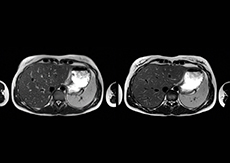

“We also love MultiVane XD for motion reduction in imaging. We find this a huge step forward. We use it in the head, and of course in the upper abdomen, and the images are outstanding most of the time. And it can be combined with dS SENSE parallel imaging for speed.” “We have compared image quality of FLAIR with MultiVane XD versus FLAIR without MultiVane XD. In 15 of the 40 patients studied, we saw motion artifacts on plain FLAIR brain images. The FLAIR images with MultiVane XD were motion-free in 39 of 40 patients and showed slight motion artifacts in only one patient.”